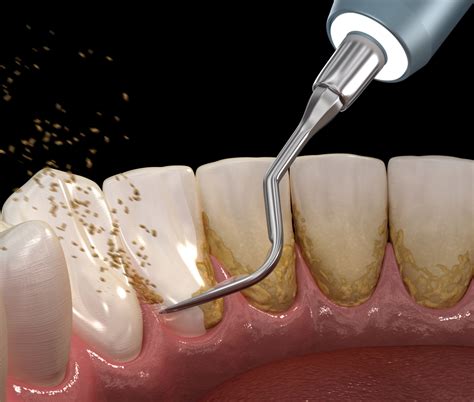

Una vez ya ha aparecido el sarro dental, sólo se puede eliminar en la clínica dental. Cuando el sarro se endurece, la forma de eliminarlo la tartrectomía ( limpieza dental) que debe ser realizada por un profesional en la clínica dental, el higienista dental.

La limpieza dental es totalmente indolora y se lleva a cabo sin anestesia. Se realiza de forma manual y también con la ayuda de ultrasonidos que desprenden el sarro del diente. En algunos pacientes con una elevada sensibilidad dental puede resultar un poco molesta, en este caso se puede poner un spray de lidocaína para insensibilizar un poco o hacerla con anestesia local.

En la Clínica Dental Bordon Clinic, utilizamos la tecnología de ultrasonido para la eliminación de sarro. raspado coronal indoloro, por lo que se realiza sin anestesia, donde el dentista o higienista dental lo hace manualmente. Es un tratamiento profesional de higiene dental que elimina bacterias acumuladas entre los dientes y encías.

Durante el procedimiento, el dentista usará herramientas especiales para raspar suavemente el sarro de los dientes y las encías. Si tiene sensibilidad dental o encías inflamadas, es posible que sienta algo de incomodidad durante el tratamiento.